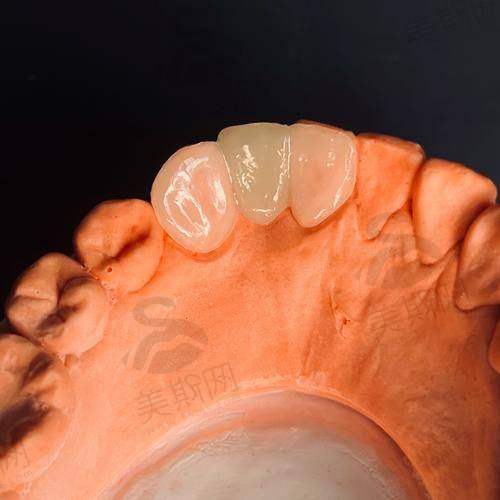

3. 美学修复中 心:主打全瓷牙贴面(超薄0.2mm)、全瓷冠修复、嵌体/高嵌体修复、牙齿美白(冷光美白、皓齿美白),采用数字化微笑设计(DSD)技术,精细还原牙齿自然形态与色泽。

2. 哈尔滨优诺博士口腔瑞士士卓曼(ITI)种植牙(含基台 + 全瓷冠):15800元/颗

8. 哈尔滨优诺博士口腔二氧化锆全瓷冠:1980元/颗